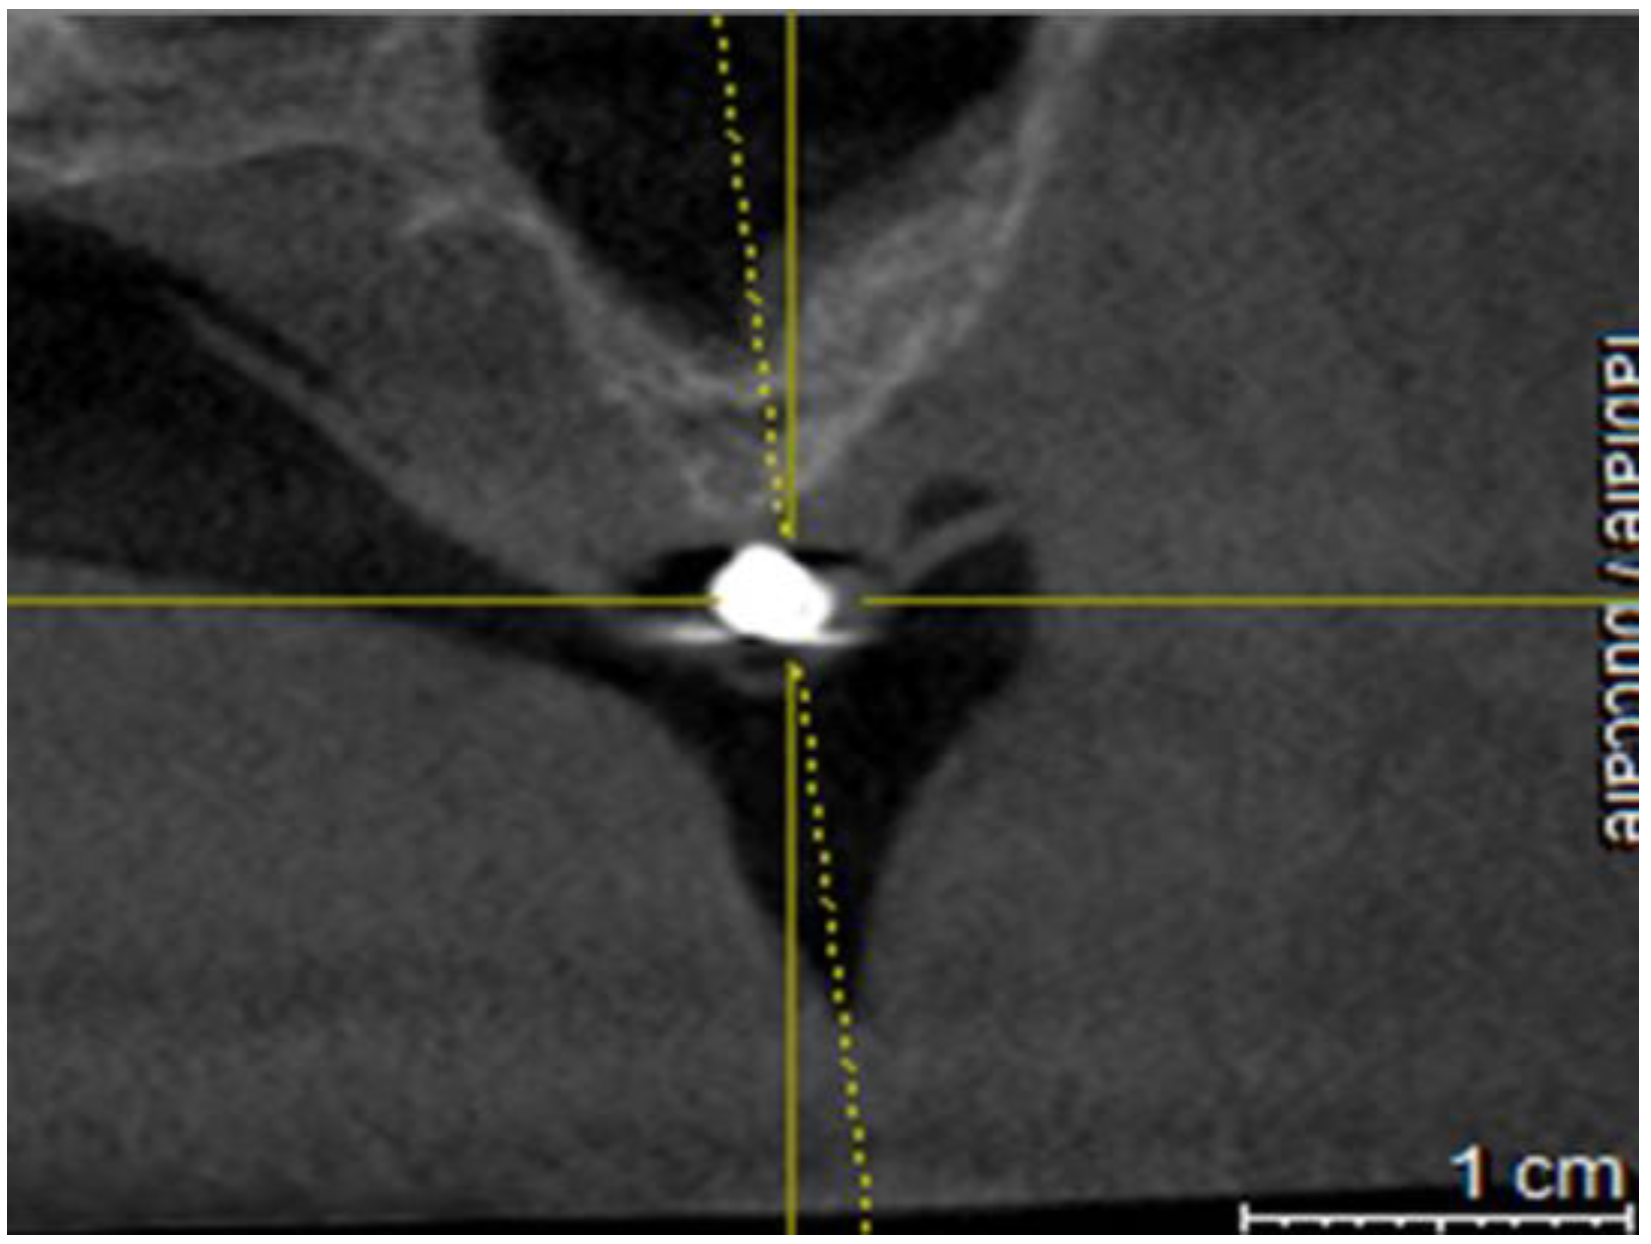

Figure 4. Cross section on CBCT.

Preprints 92994 g004

A mark was made on the mucosa in correspondence with the radiographic landmark with an indelible felt-pen.

In this way, these signs, simulating certain and visible anatomical landmarks in the CBCT, have enormously facilitated the identification of the implant site on the cortex which is a very critical phase in the free hand technique (See Table 1).